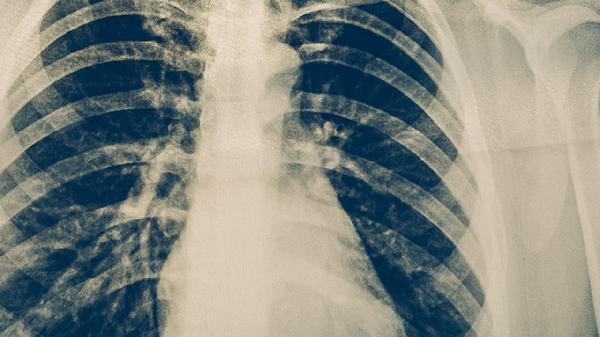

約三分之一的肺結(jié)核患者會(huì)出現(xiàn)痰中帶血或少量咯血,嚴(yán)重者可發(fā)生大咯血??┭赡芘c肺部血管受侵蝕破壞有關(guān),通常伴隨呼吸困難、面色蒼白等癥狀?;颊邞?yīng)立即臥床休息,在醫(yī)生指導(dǎo)下使用止血敏注射液、垂體后葉素注射液等藥物,必要時(shí)需進(jìn)行支氣管動(dòng)脈栓塞術(shù)。

肺結(jié)核患者應(yīng)注意保持規(guī)律作息,保證充足睡眠,避免過度勞累。飲食上應(yīng)增加優(yōu)質(zhì)蛋白攝入,如雞蛋、牛奶、瘦肉等,同時(shí)多吃新鮮蔬菜水果補(bǔ)充維生素。適當(dāng)進(jìn)行散步、太極拳等溫和運(yùn)動(dòng)有助于增強(qiáng)體質(zhì)?;颊咝鑷?yán)格遵醫(yī)囑完成6-9個(gè)月的抗結(jié)核治療,不可自行停藥,定期復(fù)查胸部X線或CT。家庭成員應(yīng)注意隔離防護(hù),保持室內(nèi)通風(fēng),對(duì)患者痰液進(jìn)行消毒處理。